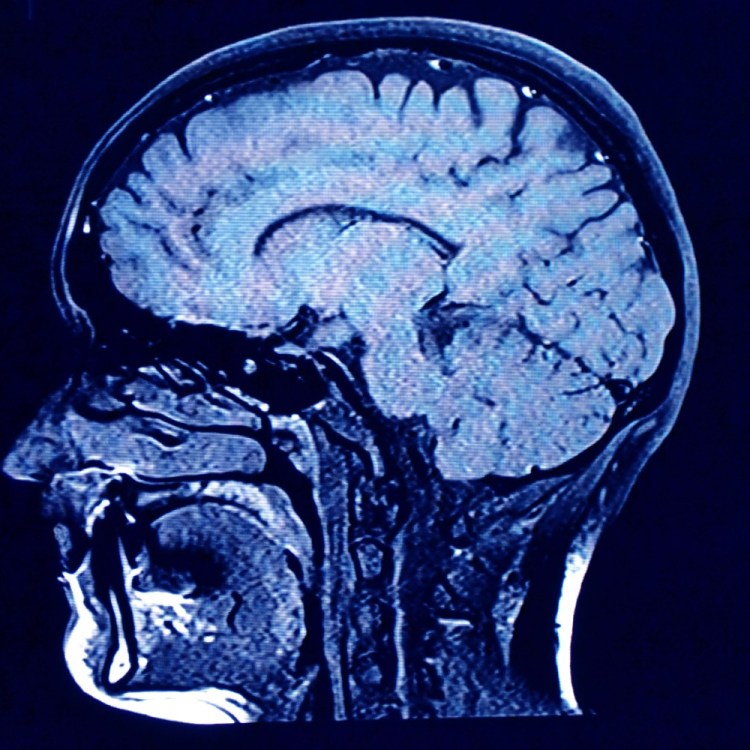

Images of a human brain. A new drug from Eli Lilly has been endorsed for approval by an FDA advisory panel.

There were concerns over side effects from donanemab, which led to some brain swelling and bleeding in some patients in the drug’s clinical trials, but the panel’s vote was unanimous in favor of approving it, as they decided the benefits outweigh the risks. As Perrone pointed out, these side effects are a result of the drug’s amyloid-targeting properties. Amyloid plaques play a crucial role in Alzheimer’s effect on the human brain.